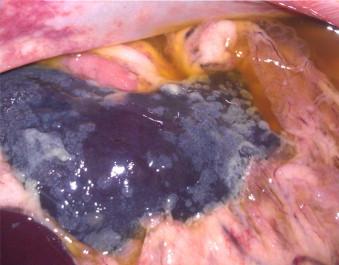

Twenty specific pathogen free cats were experimentally infected with a virulent cat-passaged type I field strain of FIPV. Eighteen cats succumbed within 2-4 weeks to effusive abdominal FIP, one survived for 6 weeks, and one seroconverted without outward signs of disease. A profound drop in the absolute count of blood lymphocytes occurred around 2 weeks post-infection (p.i.) in cats with rapid disease, while the decrease was delayed in the one cat that survived for 6 weeks. The absolute lymphocyte count of the surviving cat remained within normal range. Serum antibodies as measured by indirect immunofluorescence appeared after 2 weeks p.i. and correlated with the onset of disease signs. Viral genomic RNA was either not detectable by reverse transcription quantitative real-time PCR (RT-qPCR) or detectable only at very low levels in terminal tissues not involved directly in the infection, including hepatic and renal parenchyma, cardiac muscle, lung or popliteal lymph node. High tissue virus loads were measured in severely affected tissues such as the omentum, mesenteric lymph nodes and spleen. High levels of viral genomic RNA were also detected in whole ascitic fluid, with the cellular fraction containing 10-1000 times more viral RNA than the supernatant. Replicating virus was strongly associated with macrophages by immunohistochemistry. Virus was usually detected at relatively low levels in feces and there was no evidence of enterocyte infection. Viral genomic RNA was not detected at the level of test sensitivity in whole blood, plasma, or the white cell fraction in terminal samples from the 19 cats that succumbed or in the single survivor. These studies reconfirmed the effect of lymphopenia on disease outcome. FIPV genomic RNA was also found to be highly macrophage associated within diseased tissues and effusions as determined by RT-qPCR and immunohistochemistry but was not present in blood.

20只无特定病原体的猫被实验性感染了一种强毒的猫传代I型猫传染性腹膜炎病毒(FIPV)野毒株。18只猫在2 - 4周内死于渗出性腹部FIP,1只存活了6周,1只血清转化但无疾病外在体征。快速发病的猫在感染后约2周外周血淋巴细胞绝对计数显著下降,而存活6周的那只猫淋巴细胞计数下降延迟。存活猫的绝对淋巴细胞计数保持在正常范围内。通过间接免疫荧光法检测,血清抗体在感染后2周出现,并与疾病体征的出现相关。通过逆转录定量实时PCR(RT-qPCR),在未直接参与感染的终末组织(包括肝实质、肾实质、心肌、肺或腘窝淋巴结)中,病毒基因组RNA要么检测不到,要么仅能在极低水平检测到。在严重受影响的组织如大网膜、肠系膜淋巴结和脾脏中检测到高组织病毒载量。在整个腹水液中也检测到高水平的病毒基因组RNA,细胞部分所含病毒RNA比上清液多10 - 1000倍。通过免疫组织化学,复制病毒与巨噬细胞密切相关。在粪便中通常检测到相对较低水平的病毒,且没有肠上皮细胞感染的证据。在19只死亡猫或唯一幸存者的终末样本的全血、血浆或白细胞部分中,在检测灵敏度水平未检测到病毒基因组RNA。这些研究再次证实了淋巴细胞减少对疾病结局的影响。通过RT-qPCR和免疫组织化学确定,FIPV基因组RNA在患病组织和渗出液中也与巨噬细胞高度相关,但在血液中不存在。